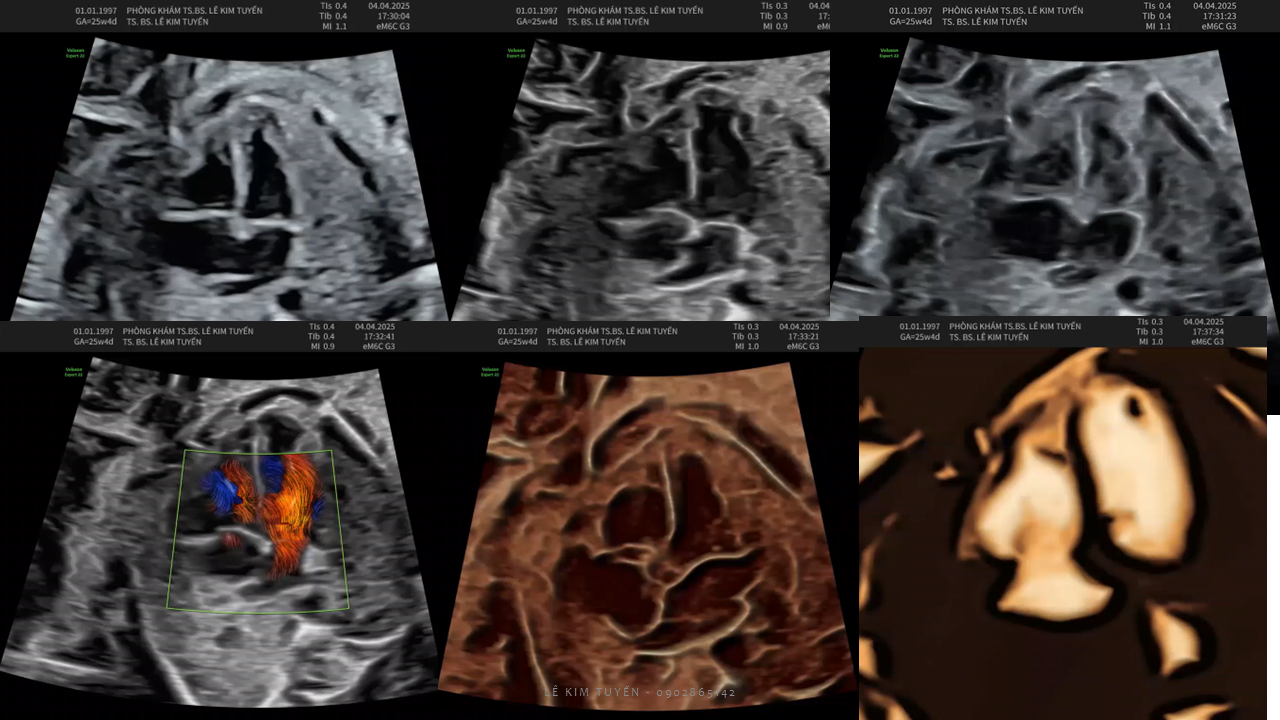

Siêu âm tim thai - Các kỹ thuật hiện đại

TS. BS. Lê Kim Tuyến

Bệnh viện Tim Tâm Đức